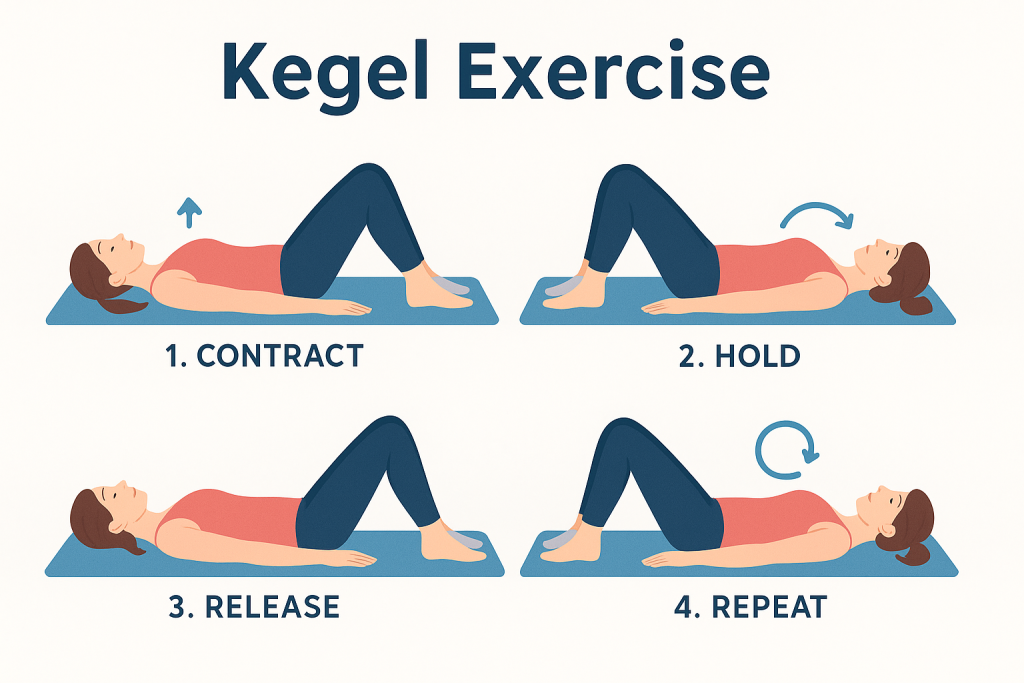

1. ออกกำลังกาย Kegel Exercise สำหรับผู้หญิง

เป็นท่าบริหารกล้ามเนื้ออุ้งเชิงกราน (Pelvic Floor) ที่ช่วยกระชับช่องคลอด ควบคุมการขับถ่าย และเพิ่มความรู้สึกขณะมีเพศสัมพันธ์

✅ วิธีทำ: ขมิบกล้ามเนื้อเหมือนตอนกลั้นปัสสาวะ ค้างไว้ 5 วินาที แล้วปล่อย ทำวันละ 10–15 ครั้ง วันละ 3 เซ็ต